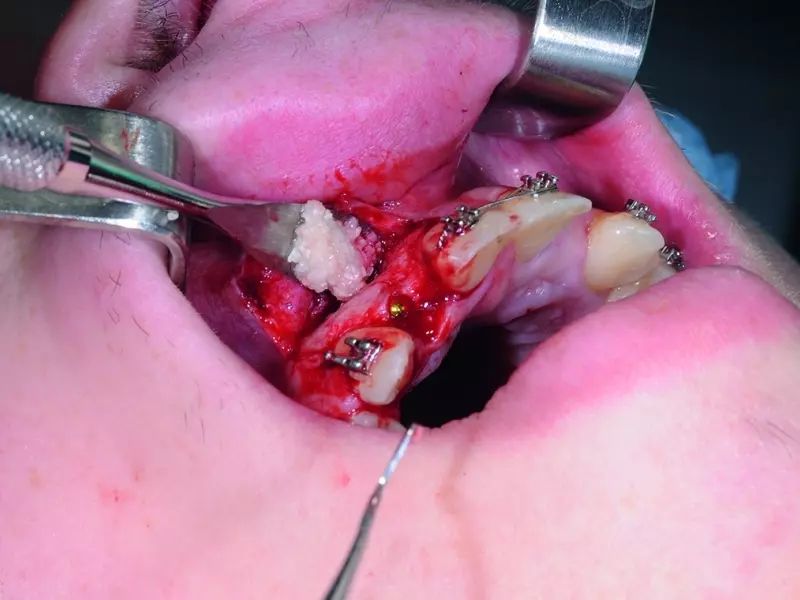

Pacjentka zgłosiła się w celu przeprowadzenia zabiegu augmentacji zębodołu po 14 dniach od usunięcia zęba, ponieważ ze względów medycznych nie była możliwa natychmiastowa augmentacja z typem III według klasyfikacji poekstrakcyjnych ubytków wyrostka zębodołowego. Jest to najtrudniejszy do leczenia rodzaj defektów wyrostka, który wymaga zabiegów augmentacji i często wieloetapowej metody, co jest czasochłonne.

Tkanki miękkie wokół ubytku odpreparowano i utworzono podokostnową kieszeń nad ubytkiem, która była o ok. 2 mm większa niż ubytek. W kieszeni umieszczono kolagenową błonę resorbowalną, odizolowując płat śluzówkowo-okostnowy od światła zębodołu. Zębodół wypełniono substytutem kości i całość pokryto sztywniejszą błoną kolagenową niemającą po założeniu do zębodołu tendencji do zapadania i nierwącą się przy zakładaniu szwów i o stosunkowo długim, bo wynoszącym 6 miesięcy, czasie resorpcji. Całość unieruchomiono przez założenie resorbowalnych szwów.